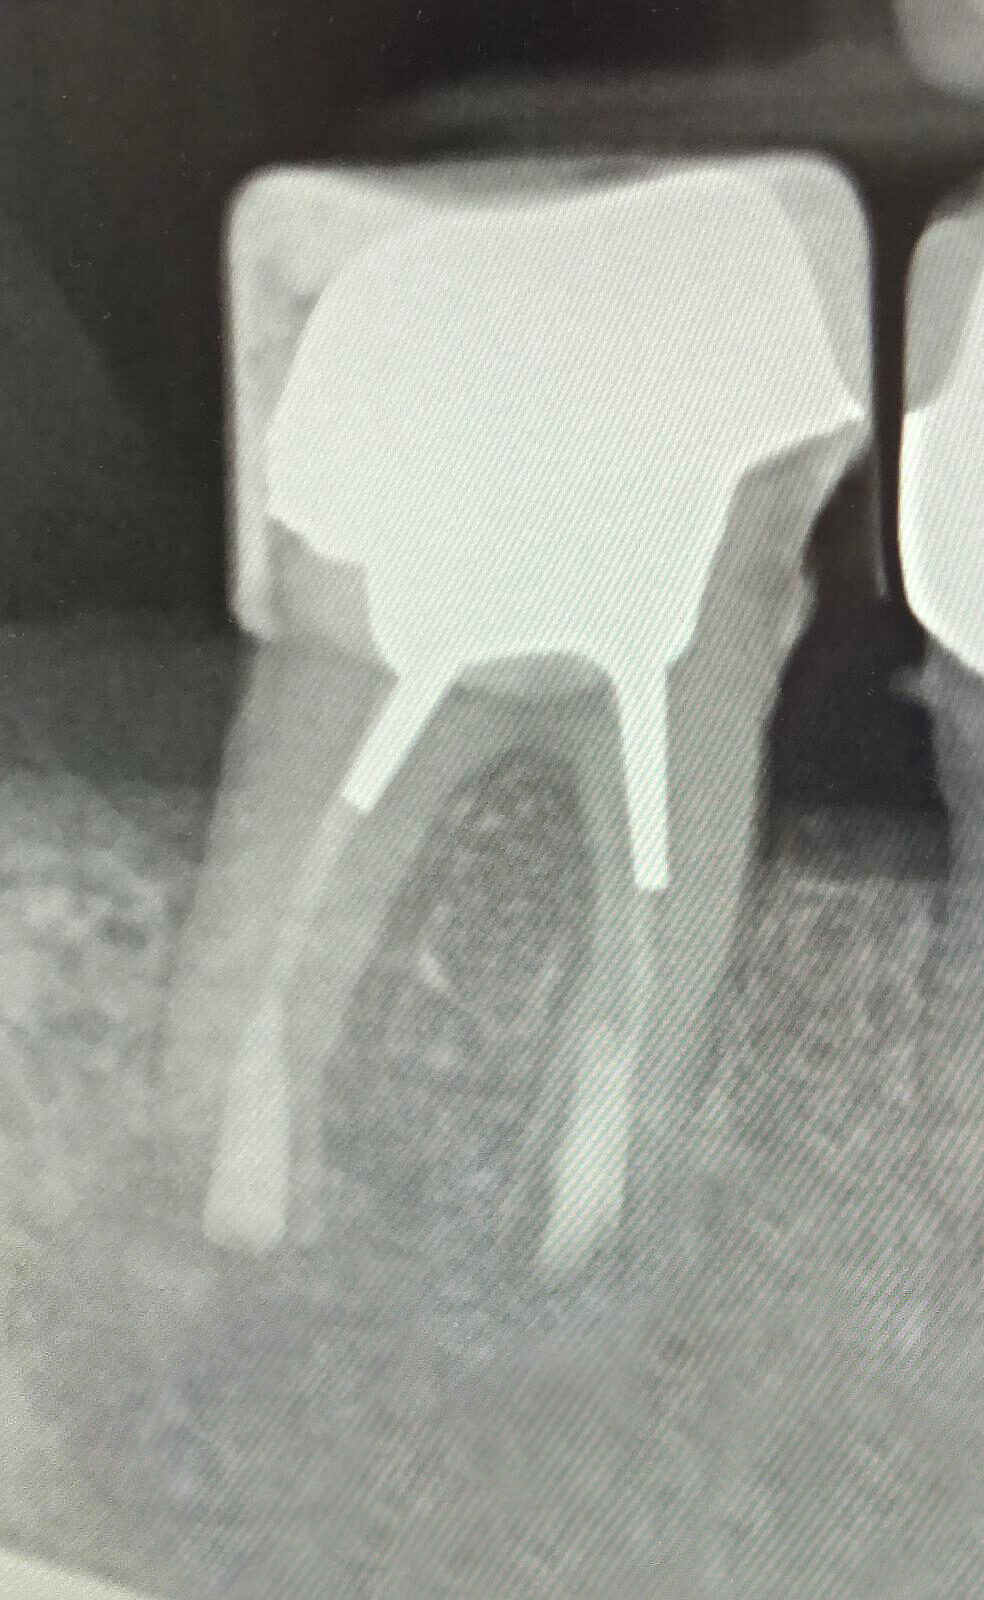

Zahnärztliches Röntgenbild mit mehreren Backenzähnen – Darstellung von Wurzelkanalbehandlungen und Füllungen zur Diagnostik in der Zahnklinik Nordhorn

Vorher